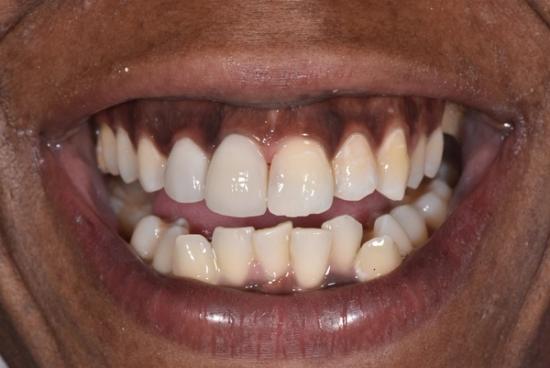

After Photo